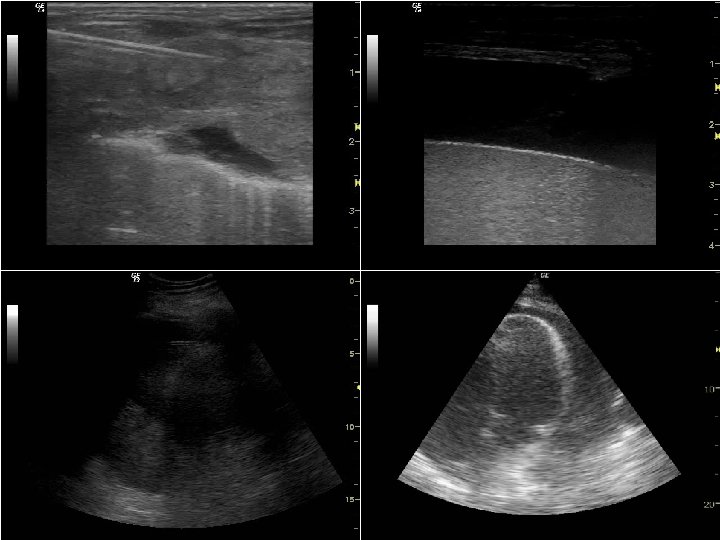

ECO SEPSI LA FONTE • L’ecografia in valutazione primaria e secondaria (testapiedi) consente di identificare il 75 -85% delle fonti settiche, congiuntamente alla clinica • In caso di infezione di origine toracica si riscontra di regola una sindrome focale (versamento pleurico, impegno interstiziale localizzato, consolidamento) • Nell’addome il riscontro di versamento endoperitoneale non localizzato (con o senza gas) è suggestivo per una patologia diffusa, mentre le infezioni focali presentano quadri specifici (indicativi per colecistite, diverticolite, ascessi, ostruzione delle vie urinarie, ecc. ) • Altre infezioni focali (osteo-articolari o dei tessuti molli) sono più facilmente evidenti – l’ecografia può fornire elementi aggiuntivi (p. es. presenza di gas)

ECO SEPSI LA FUNZIONE T 1 r T 3 r TIIr T 5 r T 4 r T 2 r T 6 r • Impegno pleurico T 3 l T 5 l T 2 l T 4 l T 6 l TDr • Impegno parenchimale • Funzione diaframma TIIl T 1 l TDl A 1 r A 1 l B

ECO SEPSI RESPIRAZIONE LA FUNZIONE B • Il grado di impegno parenchimale polmonare (interstiziale e da consolidamento) correla inversamente con la prognosi e con la possibilità di recupero dell’autonomia nella ventilazione • Anche la funzione diaframmatica in respiro spontaneo (valutabile con il movimento caudale delle cupole o con l’ispessimento del muscolo) può essere predittiva della possibilità di recupero dell’automomia ventilatoria • Il grado di impegno parenchimale fornisce anche una stima del postcarico dx e permette di valutare preventivamente la tolleranza al carico volemico

B ECOMONITOR T 1 r T 3 r TIIr T 5 r T 4 r T 2 r T 6 r • Impegno pleurico T 1 l T 3 l T 5 l T 2 l T 4 l T 6 l TDr • Impegno parenchimale • Funzione diaframma TIIl TDl A 1 r A 1 l

ECOMONITOR RESPIRAZIONE B • La monitorizzazione ecografica del grado di impegno parenchimale polmonare e della funzione diaframmatica consente di prevedere la necessità di supporto ventilatorio e l’evoluzione clinica • Anche la funzione diaframmatica può essere valutata ripetutamente durante fasi di respiro spontaneo per stimare la probabilitò di recupero dell’automomia ventilatoria

B ECOMONITOR Sindrome interstiziale

ECOMONITOR Consolidamento parenchimale B